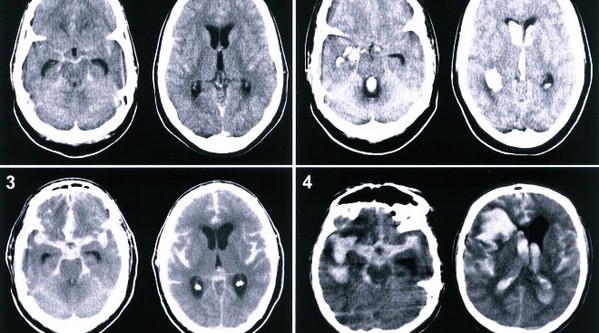

Также используется следующие диагностики:

- МРТ.

- КТ. Используется в редких случаях и тогда, когда МРТ проводить нельзя.

- ПЭТ. Данная диагностика уточняет размеры новообразования.

- МРА. Метод исследования помогает изучить сосуды, которые питают новообразование. Обязательно в кровь пациента вводится контрастное вещество.